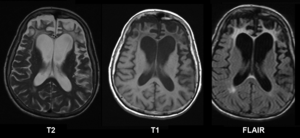

A range of neuropsychological tests are available for clarifying the nature and extent of frontal lobe dysfunction. For example, concept formation and ability to shift mental sets can be measured with the Wisconsin Card Sorting Test, planning can be assessed with the Mazes subtest of the WISC.[18] Individuals with Pick's disease will show frontal cortical atrophy on MRIs.[19] Frontal impairment due to head injuries, tumours or cerebrovascular disease will also be apparent on brain imaging.[13]